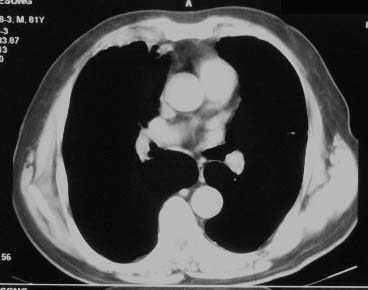

右肺上叶肿块,其远侧段肺组织炎性渗出性改变,局部胸膜粘连,肺门侧边缘光滑锐利,可见结节样病灶;右肺尖纤维索条状影,局部肺纹理纠集,纵隔窗窗宽不合适,病灶内部情况显示不清,未见明显淋巴结肿大及钙化.

右肺中叶软组织块(挑剔一下纵隔窗窗宽不理想),其周围可见多个类圆形结节,右肺上叶尖段见斑片、索条状致影,左肺小结节。